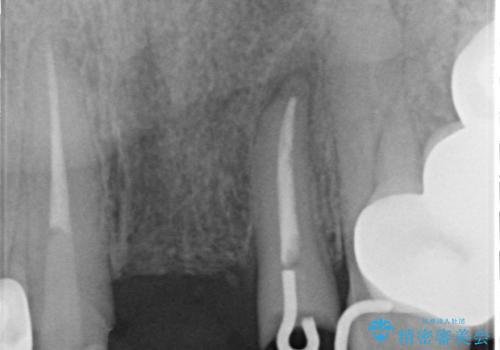

歯肉縁下カリエスも認められるため、挺出を行いセラミックブリッジを審美的に新製します。

虫歯が深くなった場合、挺出や歯周外科を行い歯周組織の状態を改善することでより安定した状態で予知性の高いセラミックブリッジを製作することが可能となります。